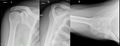

- Différentes lésion labrales post.jpg Alexandre.laedermann

19:53, 26 January 2020

1,918 × 454; 739 KB